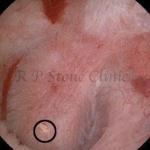

These images are taken as snap shots from the video recording of RIRS Surgery done at our hospital. These are Randall’s Plaques seen with Digital FLEX XC & Digital FLEX XC S. The cream or whitish patches are seen on the tips of RENAL PAPILLAE as seen in images below.

Randall’s Plaques may lead to the formation of Stones.

Those kidney stone patients who have Randall’s Plaques in their kidneys are more likely to form stones again (Recurrent Stones).